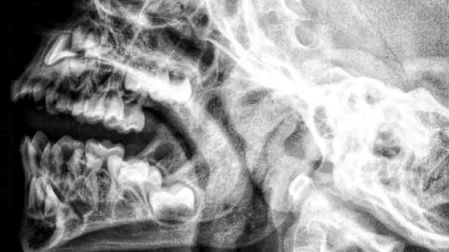

De acuerdo con el Ministerio de Salud, radiólogos dieron con el objeto en una radiografía. Un caso muy similar al que ocurrió hace varios años, cuando le encontraron a un soldado afgano un explosivo en la cabeza.

Durante la Segunda Guerra Mundial los padres desesperados introducían una aguja en un punto blando de la cabeza del recién nacido, conocido como la fontanela, donde los huesos del cráneo aún no se habían fusionado, el punto se cierra y oculta la aguja, y el bebé moría.